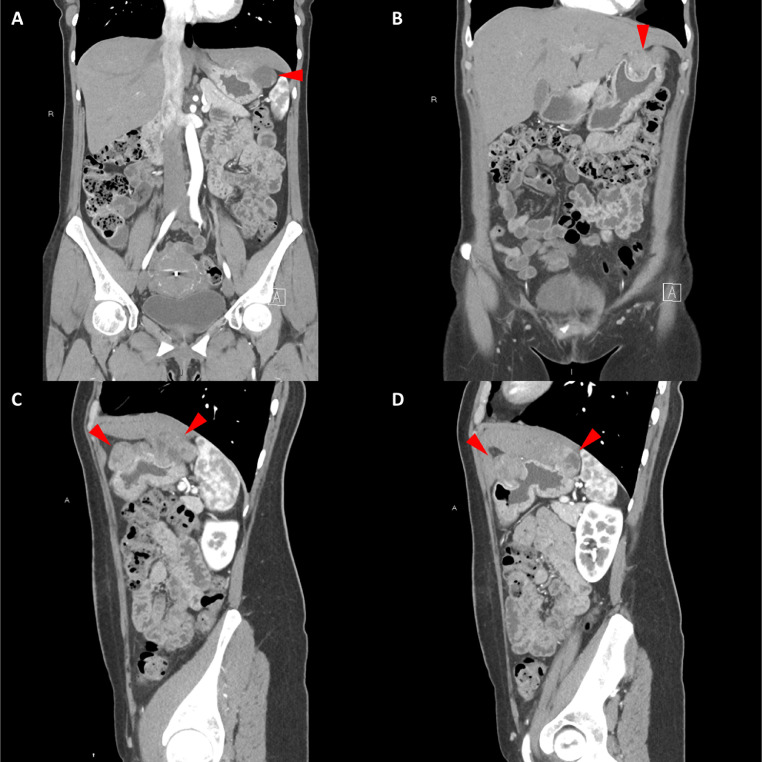

胸部、腹部和骨盆的对比增强动脉和静脉期 CT 显示多个圆形、主要是血管丰富的异质肿块,具有囊性和实性成分,起源于胃底和胃体(图 2-4)。 病变部分呈外生结构,被认为位于粘膜下层。 在颈部多发同步性副神经节瘤的情况下,贼初的鉴别诊断包括多发性副神经节瘤、多发性 GIST 以及转移性疾病。